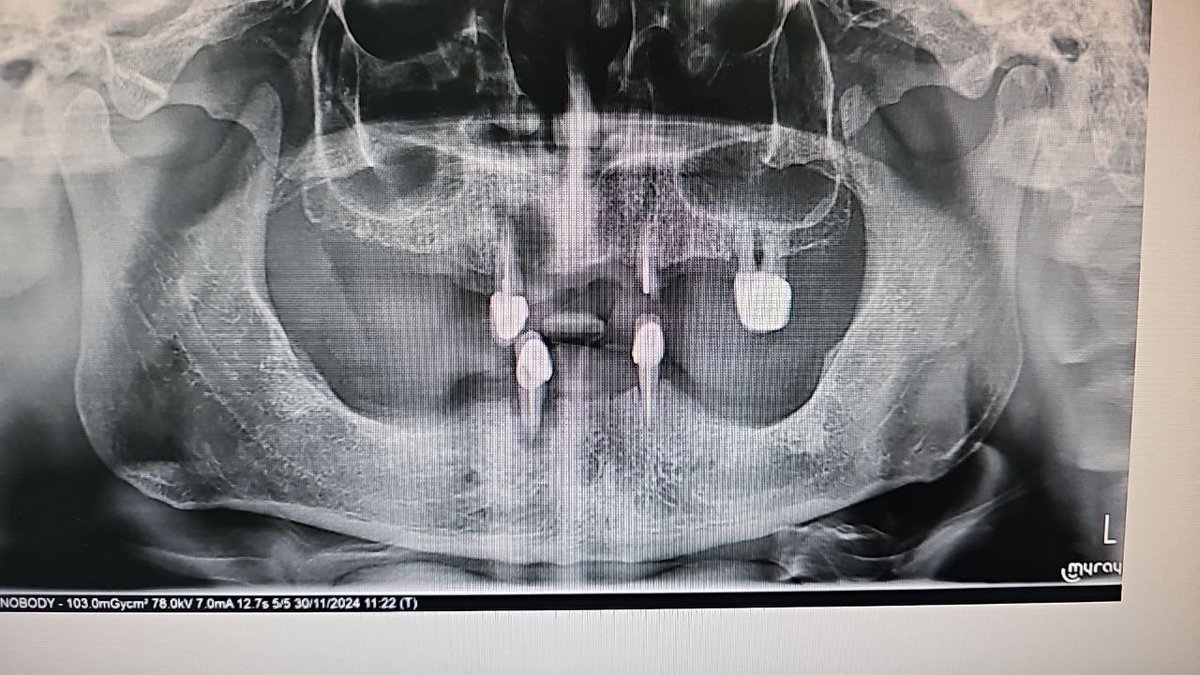

Aşırı sigara kullanımı nedeniyle ön dişleri arasında boşluk oluşan kadın, diş hekimine başvurdu.